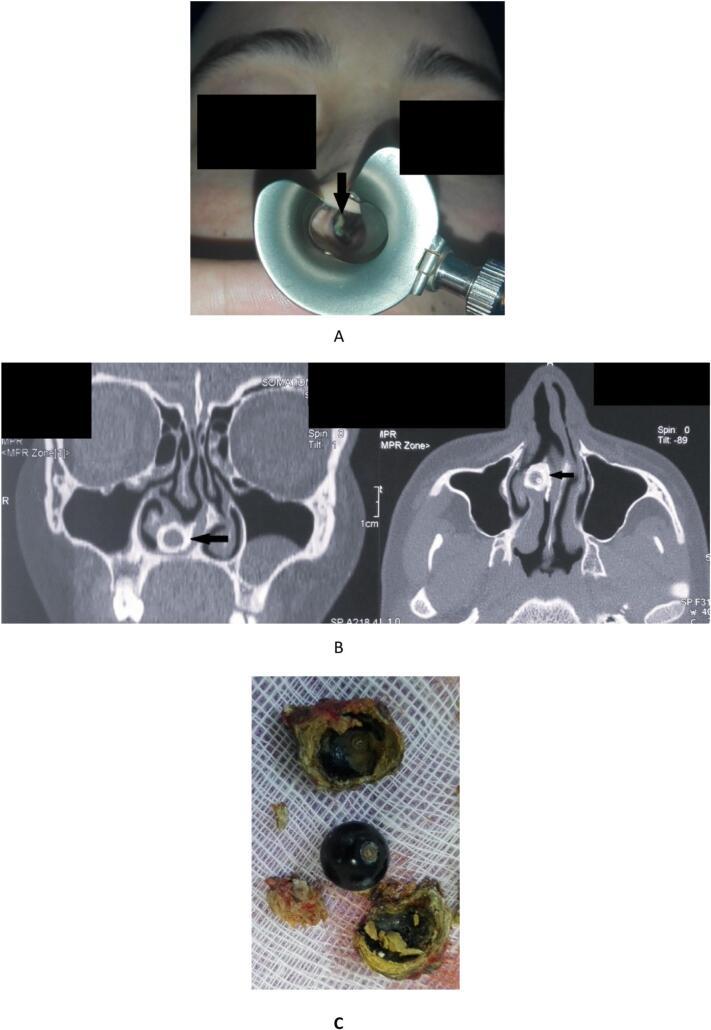

We report the case of an 18-year-old female with a year-long history of right-sided nasal obstruction and nasal discharge. Physical examination identified a mass in the right nasal cavity. A paranasal sinus CT scan confirmed the diagnosis of rhinolithiasis. The mass was successfully removed endoscopically under general anesthesia and was found to be mineralized around a synthetic pearl. The patient was discharged the following day, with no complications observed at follow-up.

我们报告一例18岁女性病例,其有长达一年的右侧鼻塞和流涕病史。体格检查发现右侧鼻腔有一肿物。鼻窦CT扫描确诊为鼻石症。在全身麻醉下通过内镜成功切除肿物,发现其围绕一颗人造珍珠矿化。患者次日出院,随访未观察到并发症。